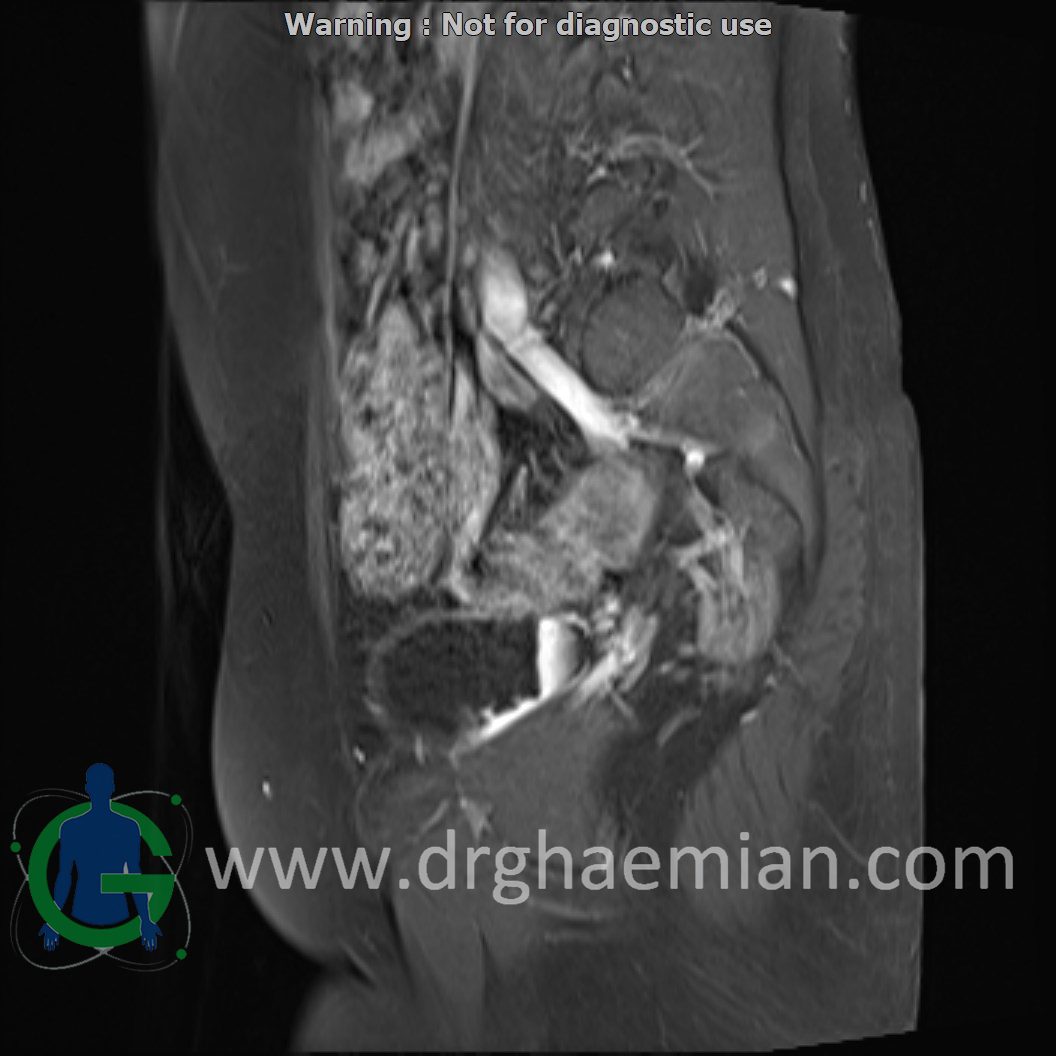

ام آر آی لگن یک روش تصویربرداری است که از طریق دستگاهی با آهنرباهای قوی و امواج رادیویی از ناحیه بین استخوان های ران تصاویری می سازد.در این کیس دیسژنزی غدد جنسی همراه با رحم و واژن هیپوپلاستیک نشان دهننده سندرم سویر ….

Complete gonadal dysgenesis with hypoplastic uterus & vagina suggestive of swyer syndrome is seen.

Clinical crrelation is recommended.